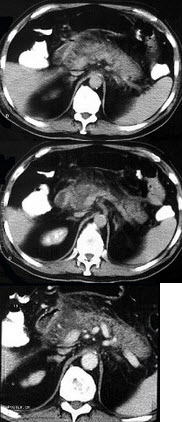

男,32岁,上腹部持续性疼痛,放射至胸背部,高热,恶心呕吐,上腹部压痛反跳痛,CT检查如图,最佳的诊断是( )

A:急性单纯性胰腺炎

B:出血坏死性胰腺炎

C:慢性胰腺炎

D:慢性胰腺炎急性发作

E:胰腺癌